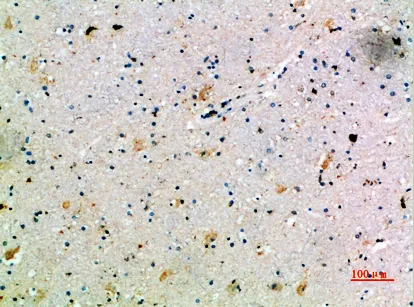

BLM Rabbit Polyclonal Antibody($99/20μL)

Cat: APRab07577

Application:IHC-P,IF-P,IF-F,ICC/IF,ELISA

Reactivity:Human,Rat,Mouse

Gene Name:BLM